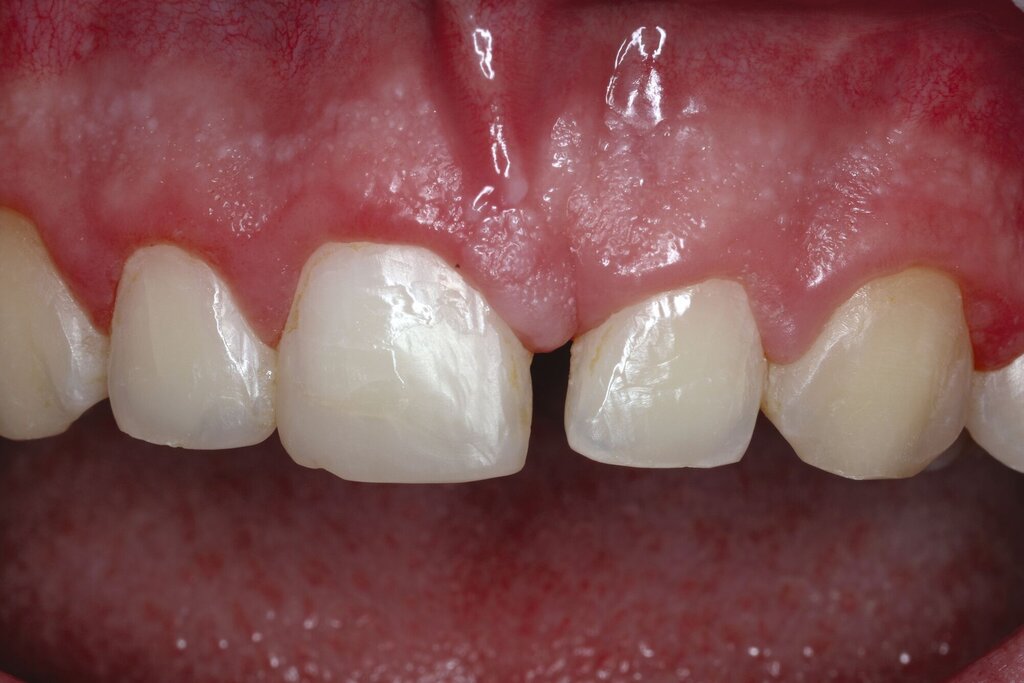

Nach einem vollständigen Zahnverlust oder auch nach einer erfolgten Dekoronation ankylosierter Zähne bietet sich insbesondere bei jungen Patienten die Versorgung mit einer Adhäsivbrücke an. Die einflügelige Adhäsivbrücke stellt eine minimalinvasive Möglichkeit zur Versorgung der Lücke bei Schneidezähnen dar (Abbildung 3). Für diese Versorgungsform liegen sehr gute Langzeitüberlebensraten von über 98 Prozent vor [Kern et al., 2017]. Einflügelige Adhäsivbrücken haben im Vergleich zu zweiflügeligen Adhäsivbrücken eine signifikant höhere Überlebensrate [Thoma et al., 2017].